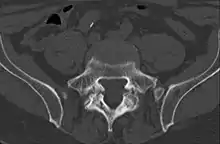

| Spondylolysis (wrong descriptions: the upper 3 arrows should be partes interarticulares) | |

Commonly known as a CT Scan or CAT scan, this form of imaging is very similar to x-ray technology but produces many more images than an x-ray does. The multiple images produce cross-sectional views not possible with an x-ray. This allows a physician or radiologist to examine the images from many more angles than an x-ray allows. For this reason the CT scan is much more accurate in detecting spondylolysis than an x-ray. Bone scintigraphy combined with CT scan is considered the gold standard which means that it is best at detecting spondylolysis.[13][15]